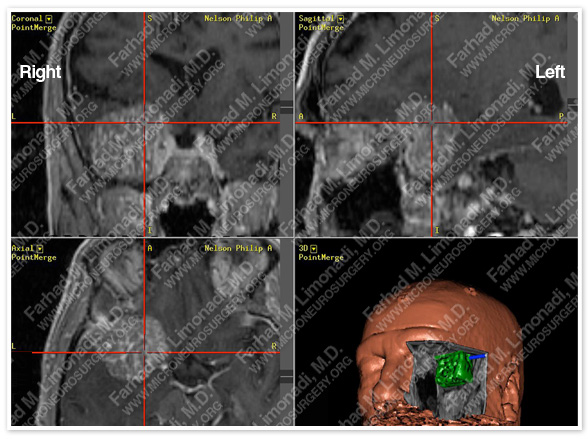

Computer Navigation

Computer simulation and modeling was utilized for precise localization of tumor (green in the right lower pic, and outlined in red circle).